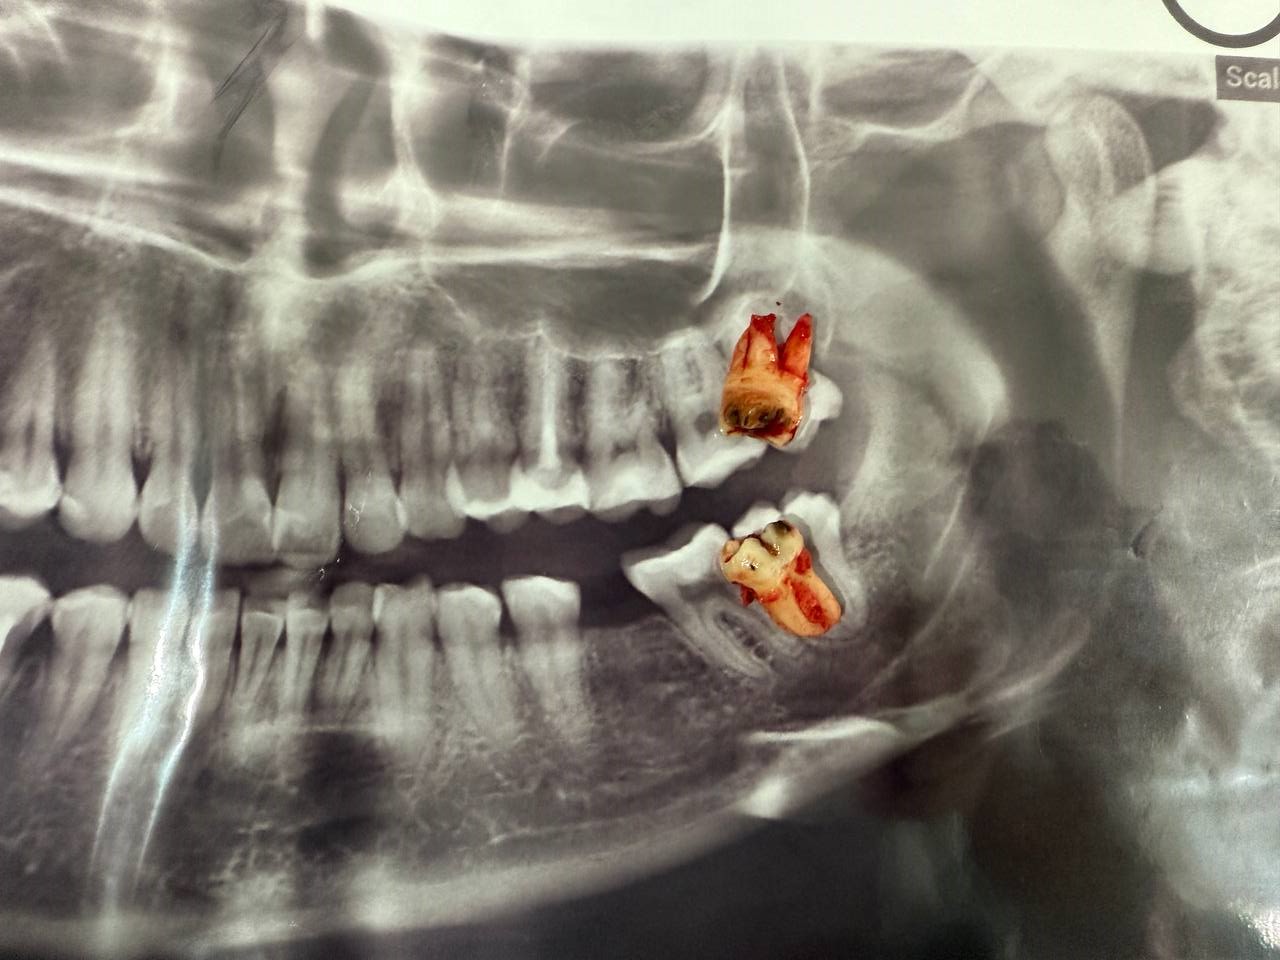

Атравматичное удаление зубов – наиболее безболезненная и щадящая процедура, которая практически не травмирует десну и костную ткань.

Зуб извлекается частями, что позволяет не травмировать окружающие ткани.

В нашей клинике осуществляется удаление самых сложных «зубов мудрости». Обычно удаление зуба под местной анестезией занимает от 10-15 минут, но иногда процедура может занять 30 или даже 60 минут и более.